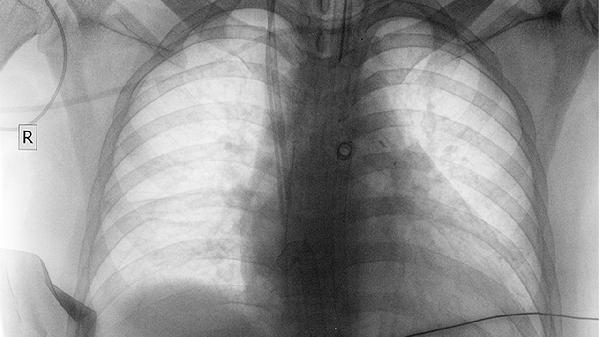

肺癌患者应严格戒烟并避免二手烟暴露,保持均衡饮食以维持免疫功能。术后患者需定期进行肺功能锻炼,监测复发迹象。不同病理类型对治疗反应差异显著,确诊后应通过基因检测制定个体化方案。出现持续咳嗽、呼吸困难等症状时须及时复查影像学。